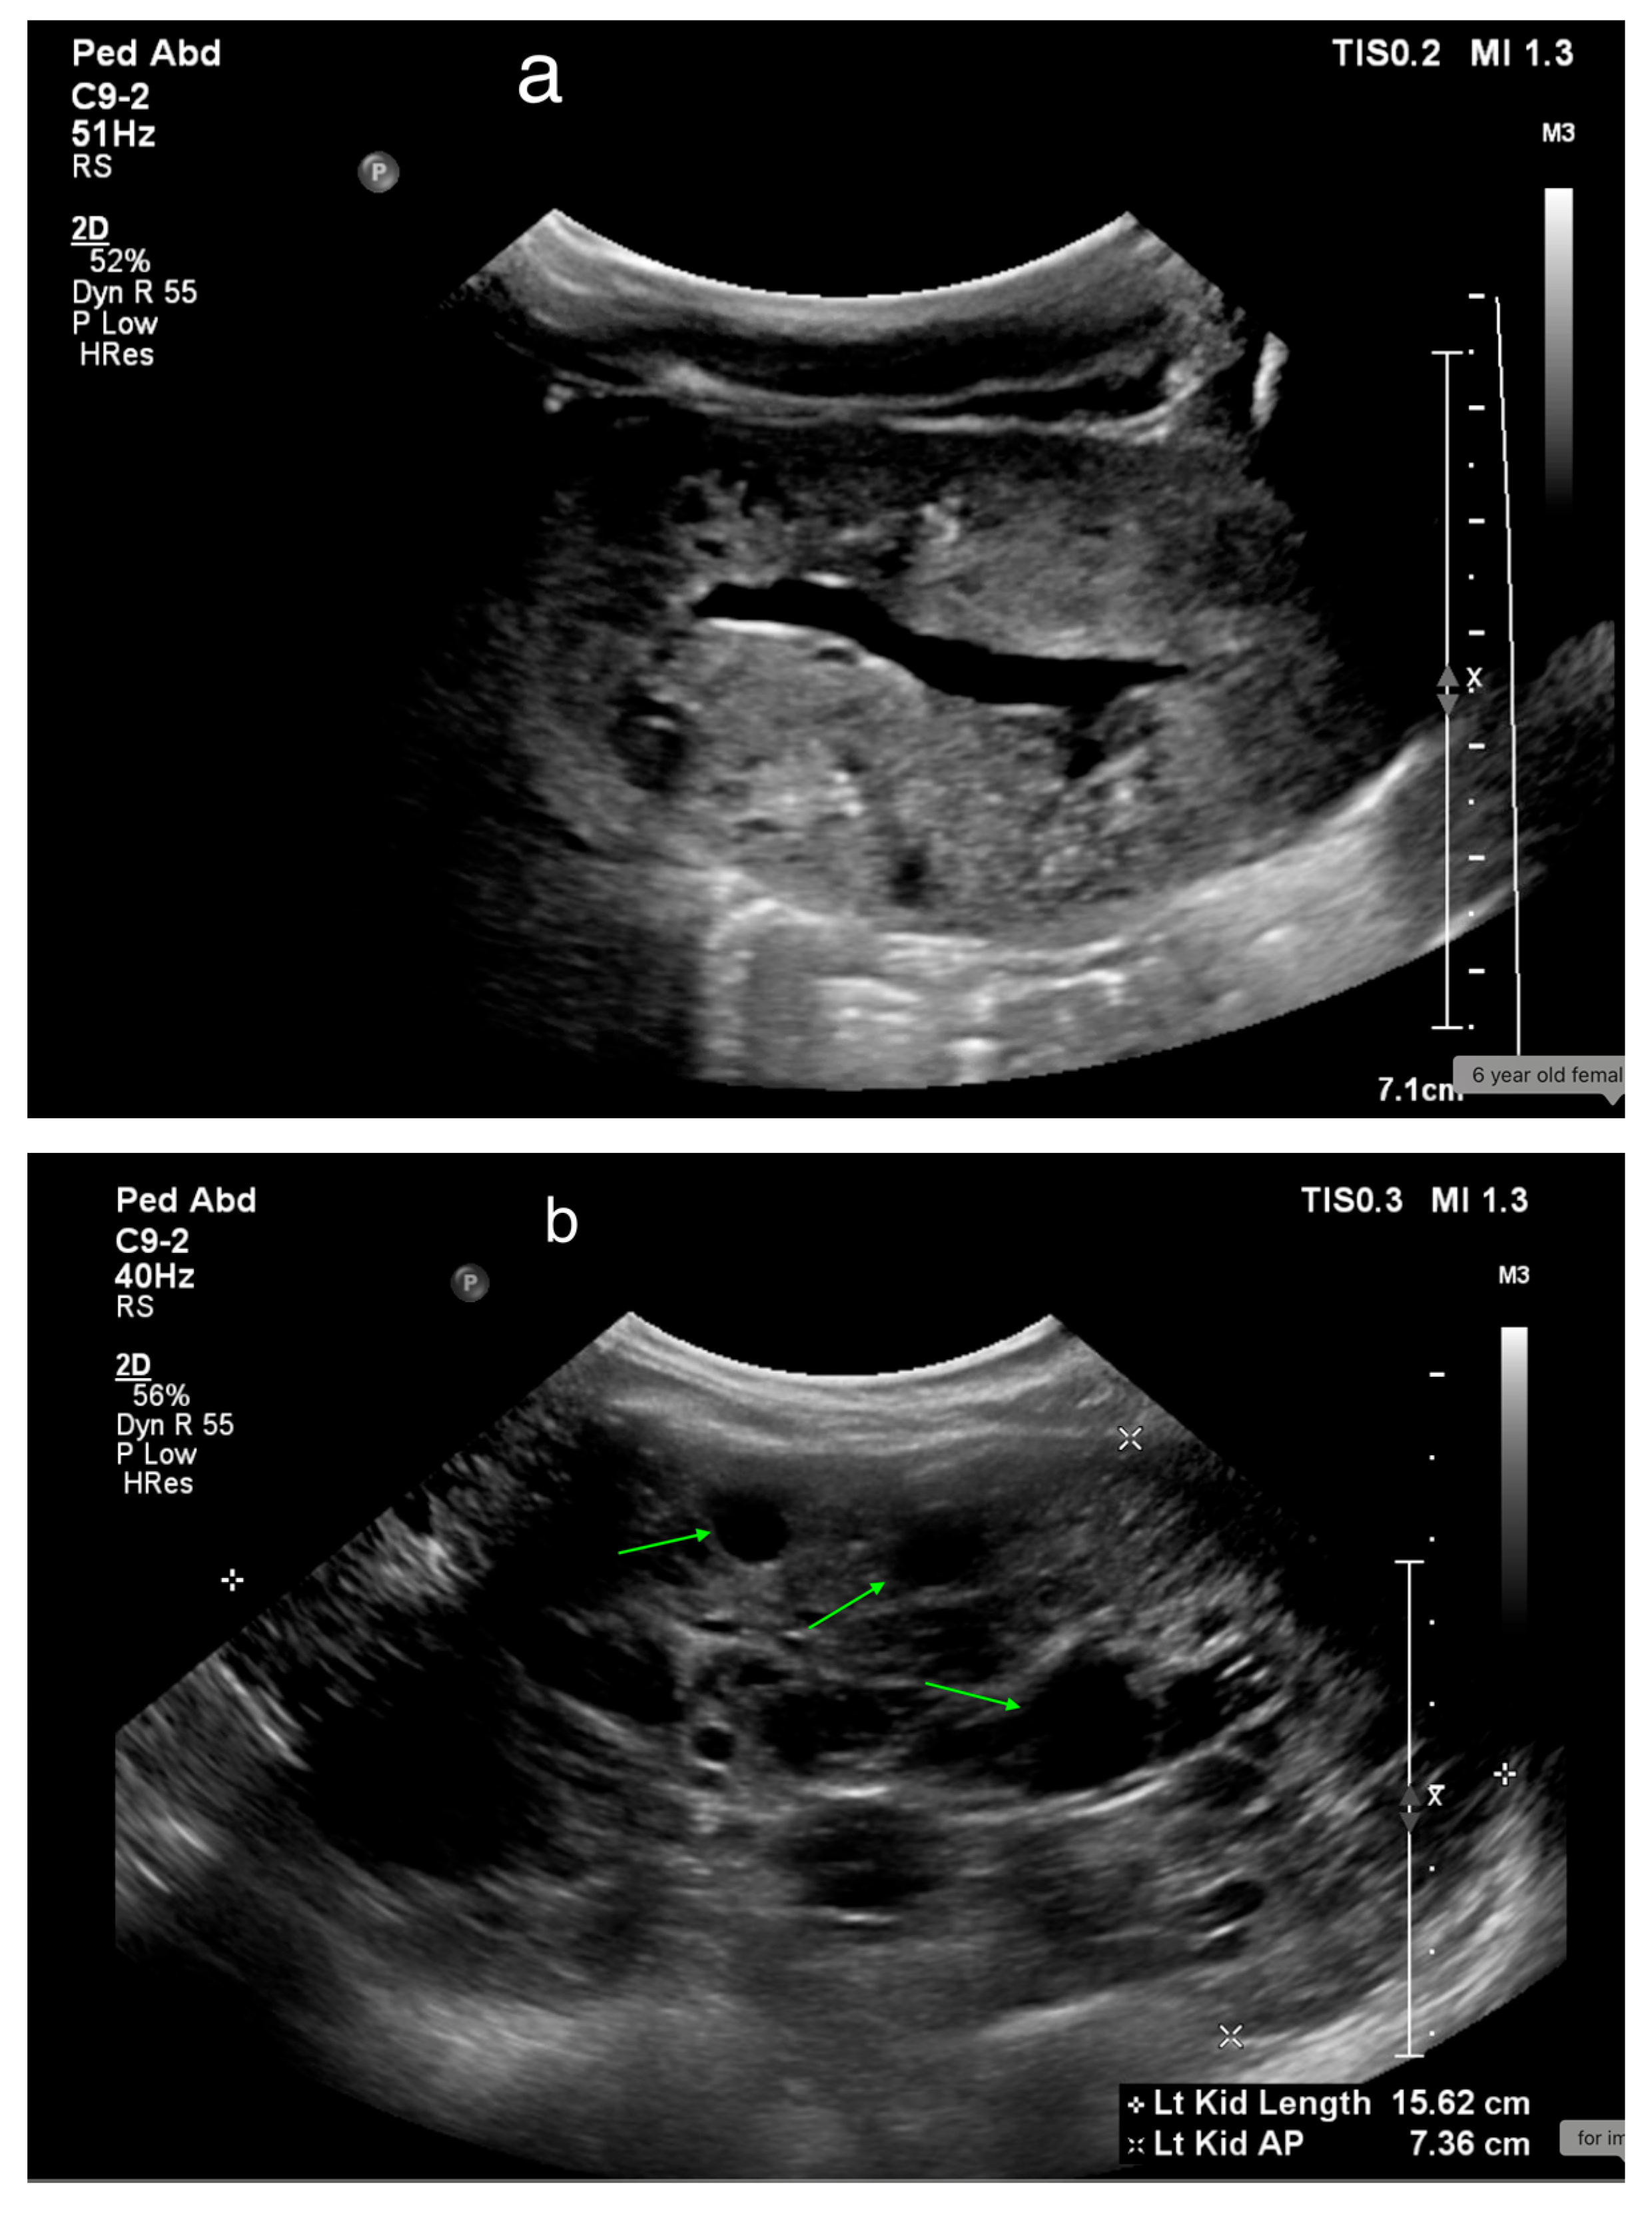

13. Obstructive Uropathy

16. Vesicoureteral Reflux